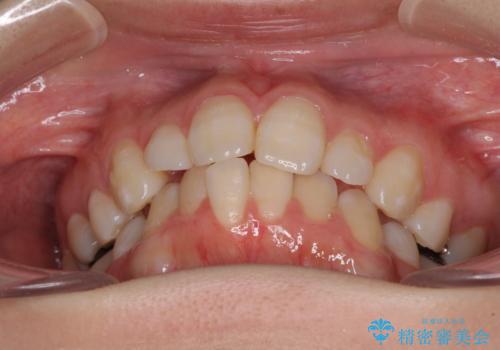

- 下顎前歯を中心に、以前行った矯正治療の後戻りが気になるとのことで来院された患者様です。

後戻りは軽度であったため、インビザライン・ライトにて治療を行うこととしました。